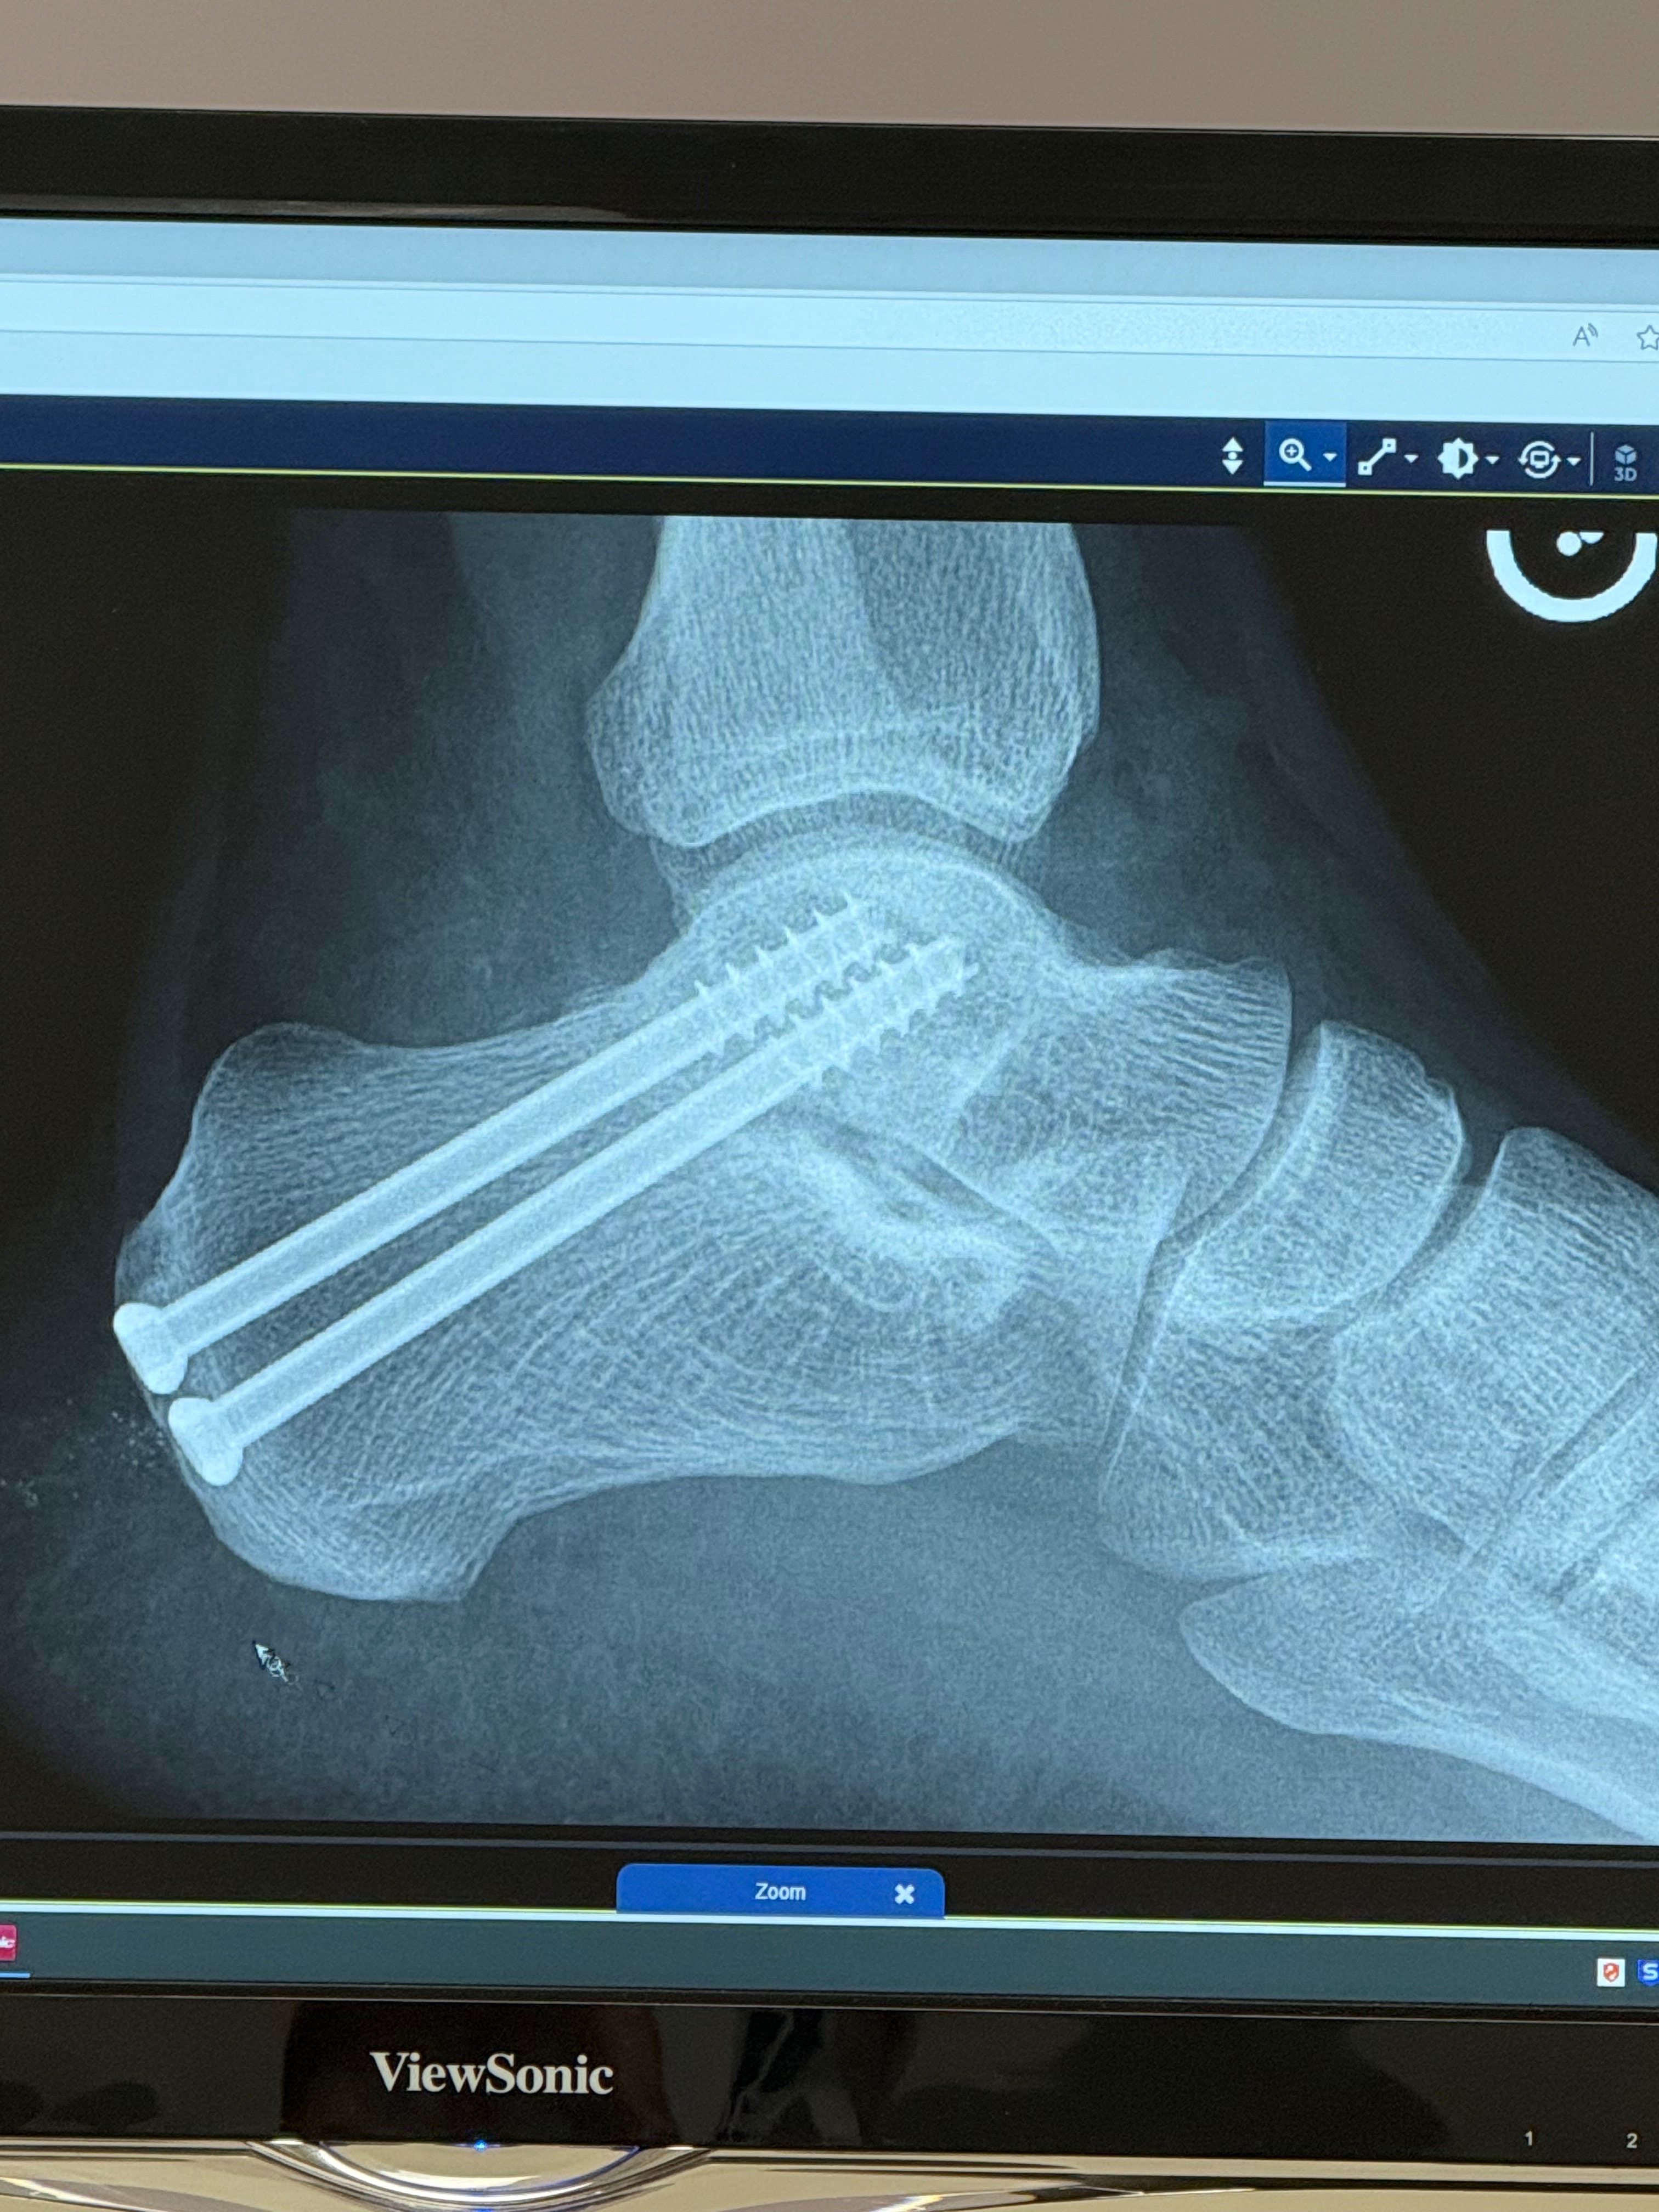

Hi, my name is Michael, and I’ve been living with severe hemophilia A and a rare condition in my left ankle called a subtalar coalition—a painful fusion of bones that were never meant to be joined. For the past 12 years, every step I've taken has been difficult. I’ve continued to work, stay active, and push through as life demands but am no longer able to do so.

My mobility and quality of life have declined to a point where I can no longer manage. After years of exhausting every non-surgical option, I’ve made the difficult decision to undergo a subtalar joint fusion surgery. This procedure will finally bring relief, but it comes with a heavy cost.